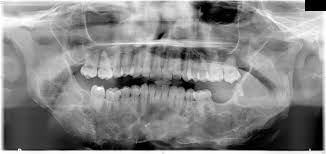

Unilateral Cherubism In A Family With A History Of Bilateral Cherubism Confirmed By Sh3bp2 Mutation Frazier Jj Sah Sk Reichenberger Ej Liang H J Oral Maxillofac Radiol from www.joomr.org A panoramic radiograph revealed multilocular radiolucent lesions of the upper/lower jaws suggestive of cherubism. Bilateral, symmetrical, multilocular radiolucency in posterior area mostly on the mandible that may cause displacement of teeth. Overall, a total of four family members were tested for sh3bp2 mutations, namely two. Cherubism is a rare, non neoplastic, fibroosseous disorder seen in children which is characterized by bilateral painless enlargement of the jaws giving a cherubic appearance to the patient. Cherubism is a rare genetic disorder that causes prominence in the lower portion in the face. Histopathology reveals multinucleated giant cells in the. Clinical, radiologic, and histopathologic characteristics confirmed the diagnosis of cherubism. Cherubism part 1 for nbde/usmle/bds/mds exams.

Cherubism is a rare genetic disorder that causes prominence in the lower portion in the face. A panoramic radiograph revealed multilocular radiolucent lesions of the upper/lower jaws suggestive of cherubism. Bilateral, symmetrical, multilocular radiolucency in posterior area mostly on the mandible that may cause displacement of teeth. Clinical, radiologic, and histopathologic characteristics confirmed the diagnosis of cherubism. Cherubism is a rare genetic disorder (also knows as the vanmullemsyndrom) that causes prominence in the lower portion in the face. Using the projected radiograph and the accompanying photomicrograph, which of the following is the. Notice the large cavities and the differences. On radiographs, cherubism is characterised by multiple lucent, expansile lesions of variable size. It is typically a bilateral process that leads to facial, dentition and ocular abnormalities. Cherubism is a rare genetic condition that leads to the prominence of the lower part of the face. On radiography, the lesions exhibit bilateral multinuclear radiolucent areas. Cherubism part 1 for nbde/usmle/bds/mds exams. Case report (англ.) // medical genetics.

It is typically a bilateral process that leads to facial, dentition and ocular abnormalities cherubism. Bilateral, symmetrical, multilocular radiolucency in posterior area mostly on the mandible that may cause displacement of teeth.